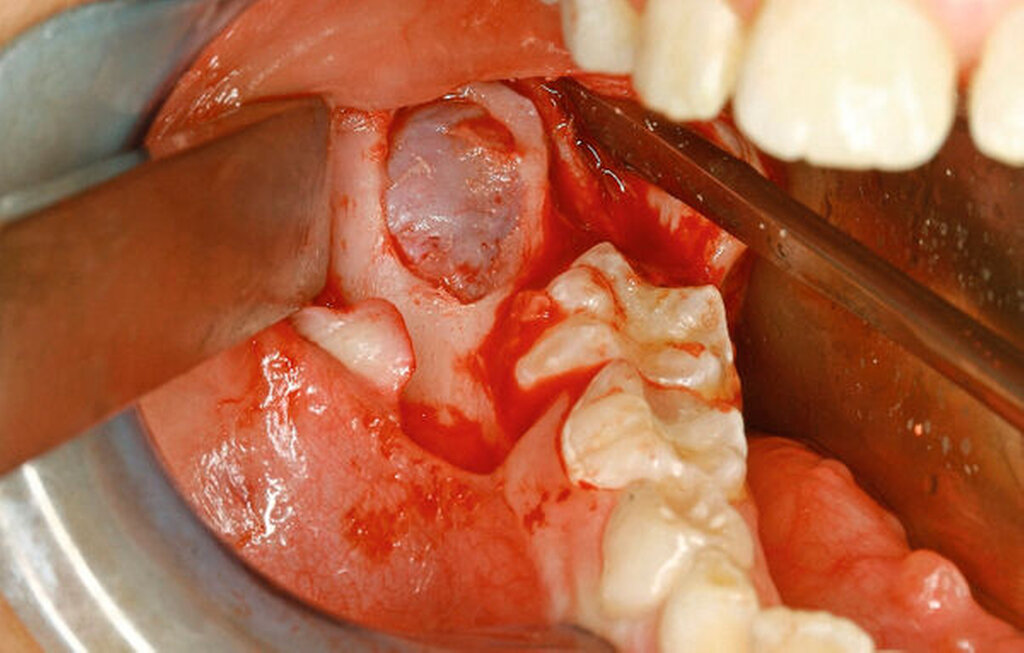

Unter der Vollnarkose erfolgte zunächst eine gründliche intraorale Inspektion, wobei sich im Bereich des Kieferwinkels rechts die knöcherne Ausbuchtung nach vestibulär deutlich darstellte (Abbildung 2). Es folgten eine Infiltrationsanästhesie im Bereich des rechten Kieferwinkels und anschließend eine marginale Inzision regio 85–46 mit Fortführung nach distal-vestibulär sowie anteriorer Entlastung. Nach Bildung eines Mukoperiostlappens wurde die Raumforderung in regio 47 mittels Osteotomie unter Schutz des N. lingualis dargestellt.

Hier zeigte sich zunächst eine bindegewebige Hülle (Abbildung 3), von der zusammen mit dem darunter liegenden Gewebe eine Probe zur intraoperativen histopathologischen Schnellschnittdiagnostik eingesendet wurde. Nach Entfernung der bindegewebigen Hülle im Bereich der Osteotomie folgte die Darstellung der sich darunter befindlichen festen Raumforderung. Diese konnte in toto enukleiert werden (Abbildungen 4 und 5). Darunter zeigte sich der retinierte und verlagerte Zahn 47. Dieser konnte im Anschluss problemlos mittels Hebel nach Bein gelöst und geborgen werden (Abbildung 6).